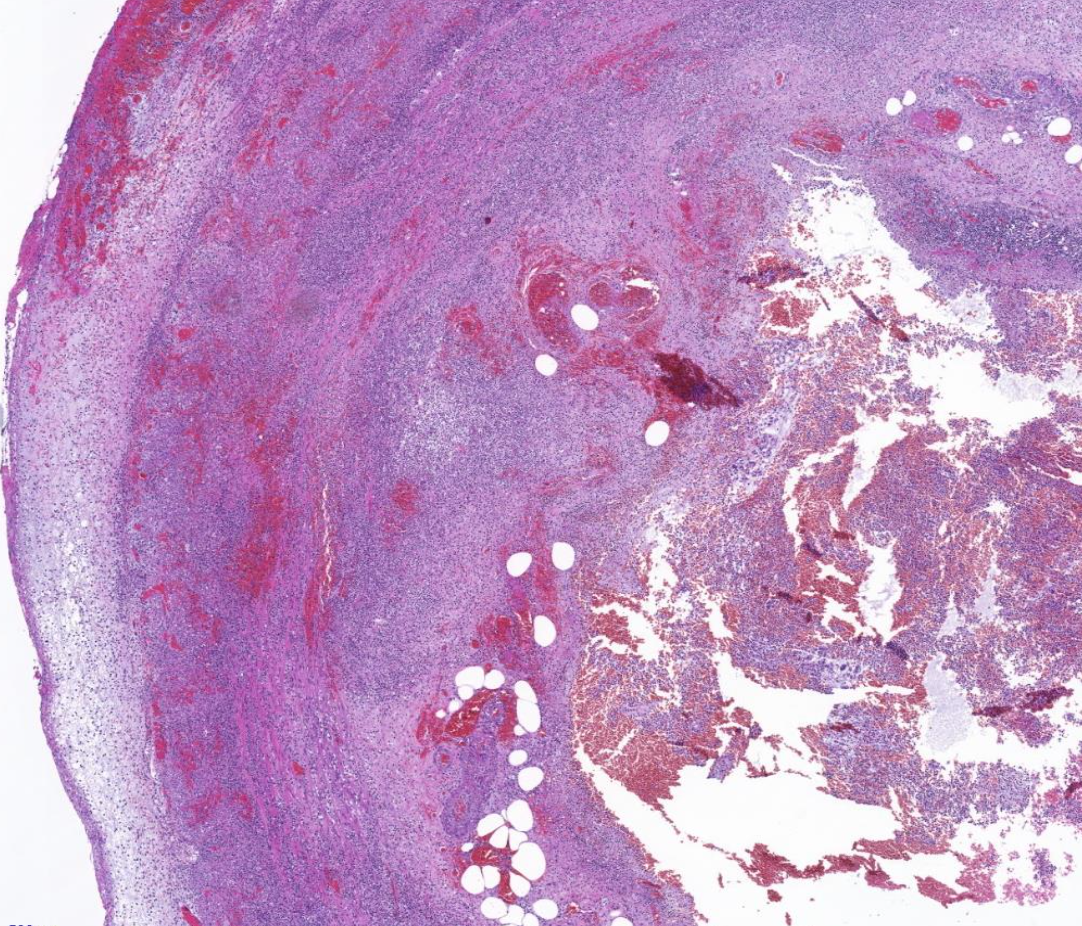

Diagnose?

Barettmetaplasie (dunkelviolett = mit Dysplasie)

Durch Reflux -> Metaplasie (nicht maligne) der Epithelien, intestinalisiertes Epithel/ Becherzellen, Biopsate mit Plattenepithel und Zylinderepithel (nur dann weiß man es ist Übergangsbereich)

Barrett-Zelle = Becherzelle